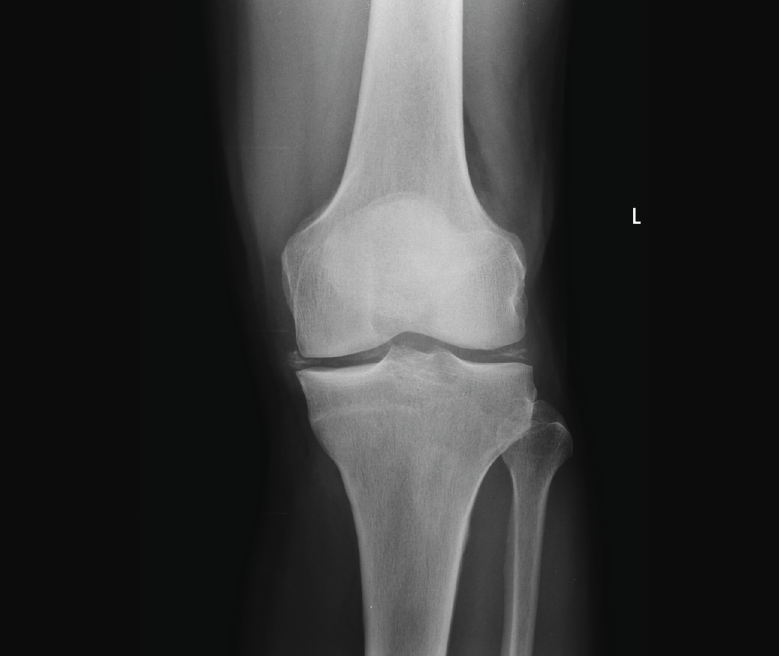

1.1.3. Rótula (Figura 3)

Figura 3. Radiografías anteroposterior y lateral de rodilla: fractura del polo superior de la rótula.